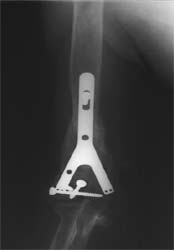

股骨远端骨折术后10年,4次手术均失败。经带锁髓内钉内 固定、植骨,骨生长因子和骨髓细胞注射,成功治愈